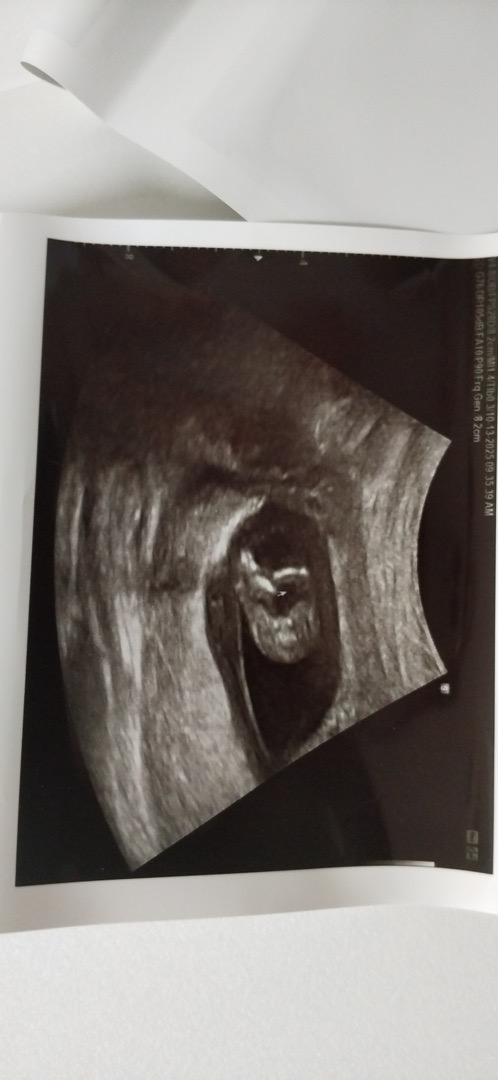

첫째둘째 그런거 없이 각도법? 어플도움 없이 낳았지만, 터울있게 생긴 우리 셋째. 셋째 ...성별중요합니다. 아시죠?왜그러는지....... 혹시 각도법 고수님들 사진보고 유추해주시면 🙇감사합니다. 오늘이 12주6일 1차 기형아검사 끝냈고 다리사이를잘 안보여줘서 힘들게 간신히 찍은 다리사이에 엉덩이뼈인지 아니면 고추가되려는 징조인지 궁금하네요~~ 옆척추사진도 다리부분은 잘안나와서 일단오늘 찍은사진 첨부합니다. 도와주세요🙌🏻🥲